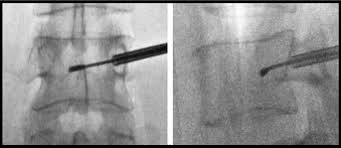

Κατά τη διάρκεια της επέμβασης , ένας ειδικός καθετήρας με ενσωματωμένο ηλεκτρόδιο εισάγεται διαδερμικά στον σπόνδυλο μέσω των αυχένων του σπονδυλικού σώματος εκατέρωθεν. Με τη χρήση της ενέργειας των ραδιοσυχνοτήτων, τα ενδοσπονδυλικά νεύρα θερμαίνονται και μαραζώνουν, παύοντας να μεταφέρουν επώδυνα ερεθίσματα.